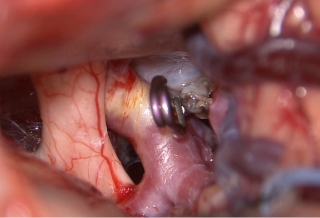

治療後

物が二重に見えるようになって発症した内頚動脈大型動脈瘤(矢印)の症例です。クリッピング術で直接動脈瘤をつぶすことができないため、バイパス術(矢印)を増設し内頚動脈を遮断することで動脈瘤を治療しました。